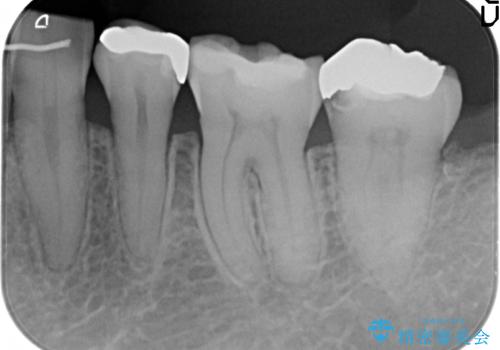

銀歯の下で虫歯の再発 拡大鏡下で行う虫歯の精密治療

- 他院で銀歯の下部に再発した虫歯の存在を指摘され、精密な治療を求めて来院されました。

銀歯下に虫歯が再発すると神経に近くなり、根管治療を必要とする可能性が高まってしまいます。

健全な歯を削らないように拡大鏡下で丁寧に虫歯を除去することで神経を温存し精密なセラミック治療を行うことができました。